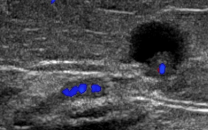

Intramammary lymph node

Benign features: oval, hypoechoic to breast tissue, echogenic vascular hilum

Malignant features: round, very hypoechoic, homogeneous, >1cm